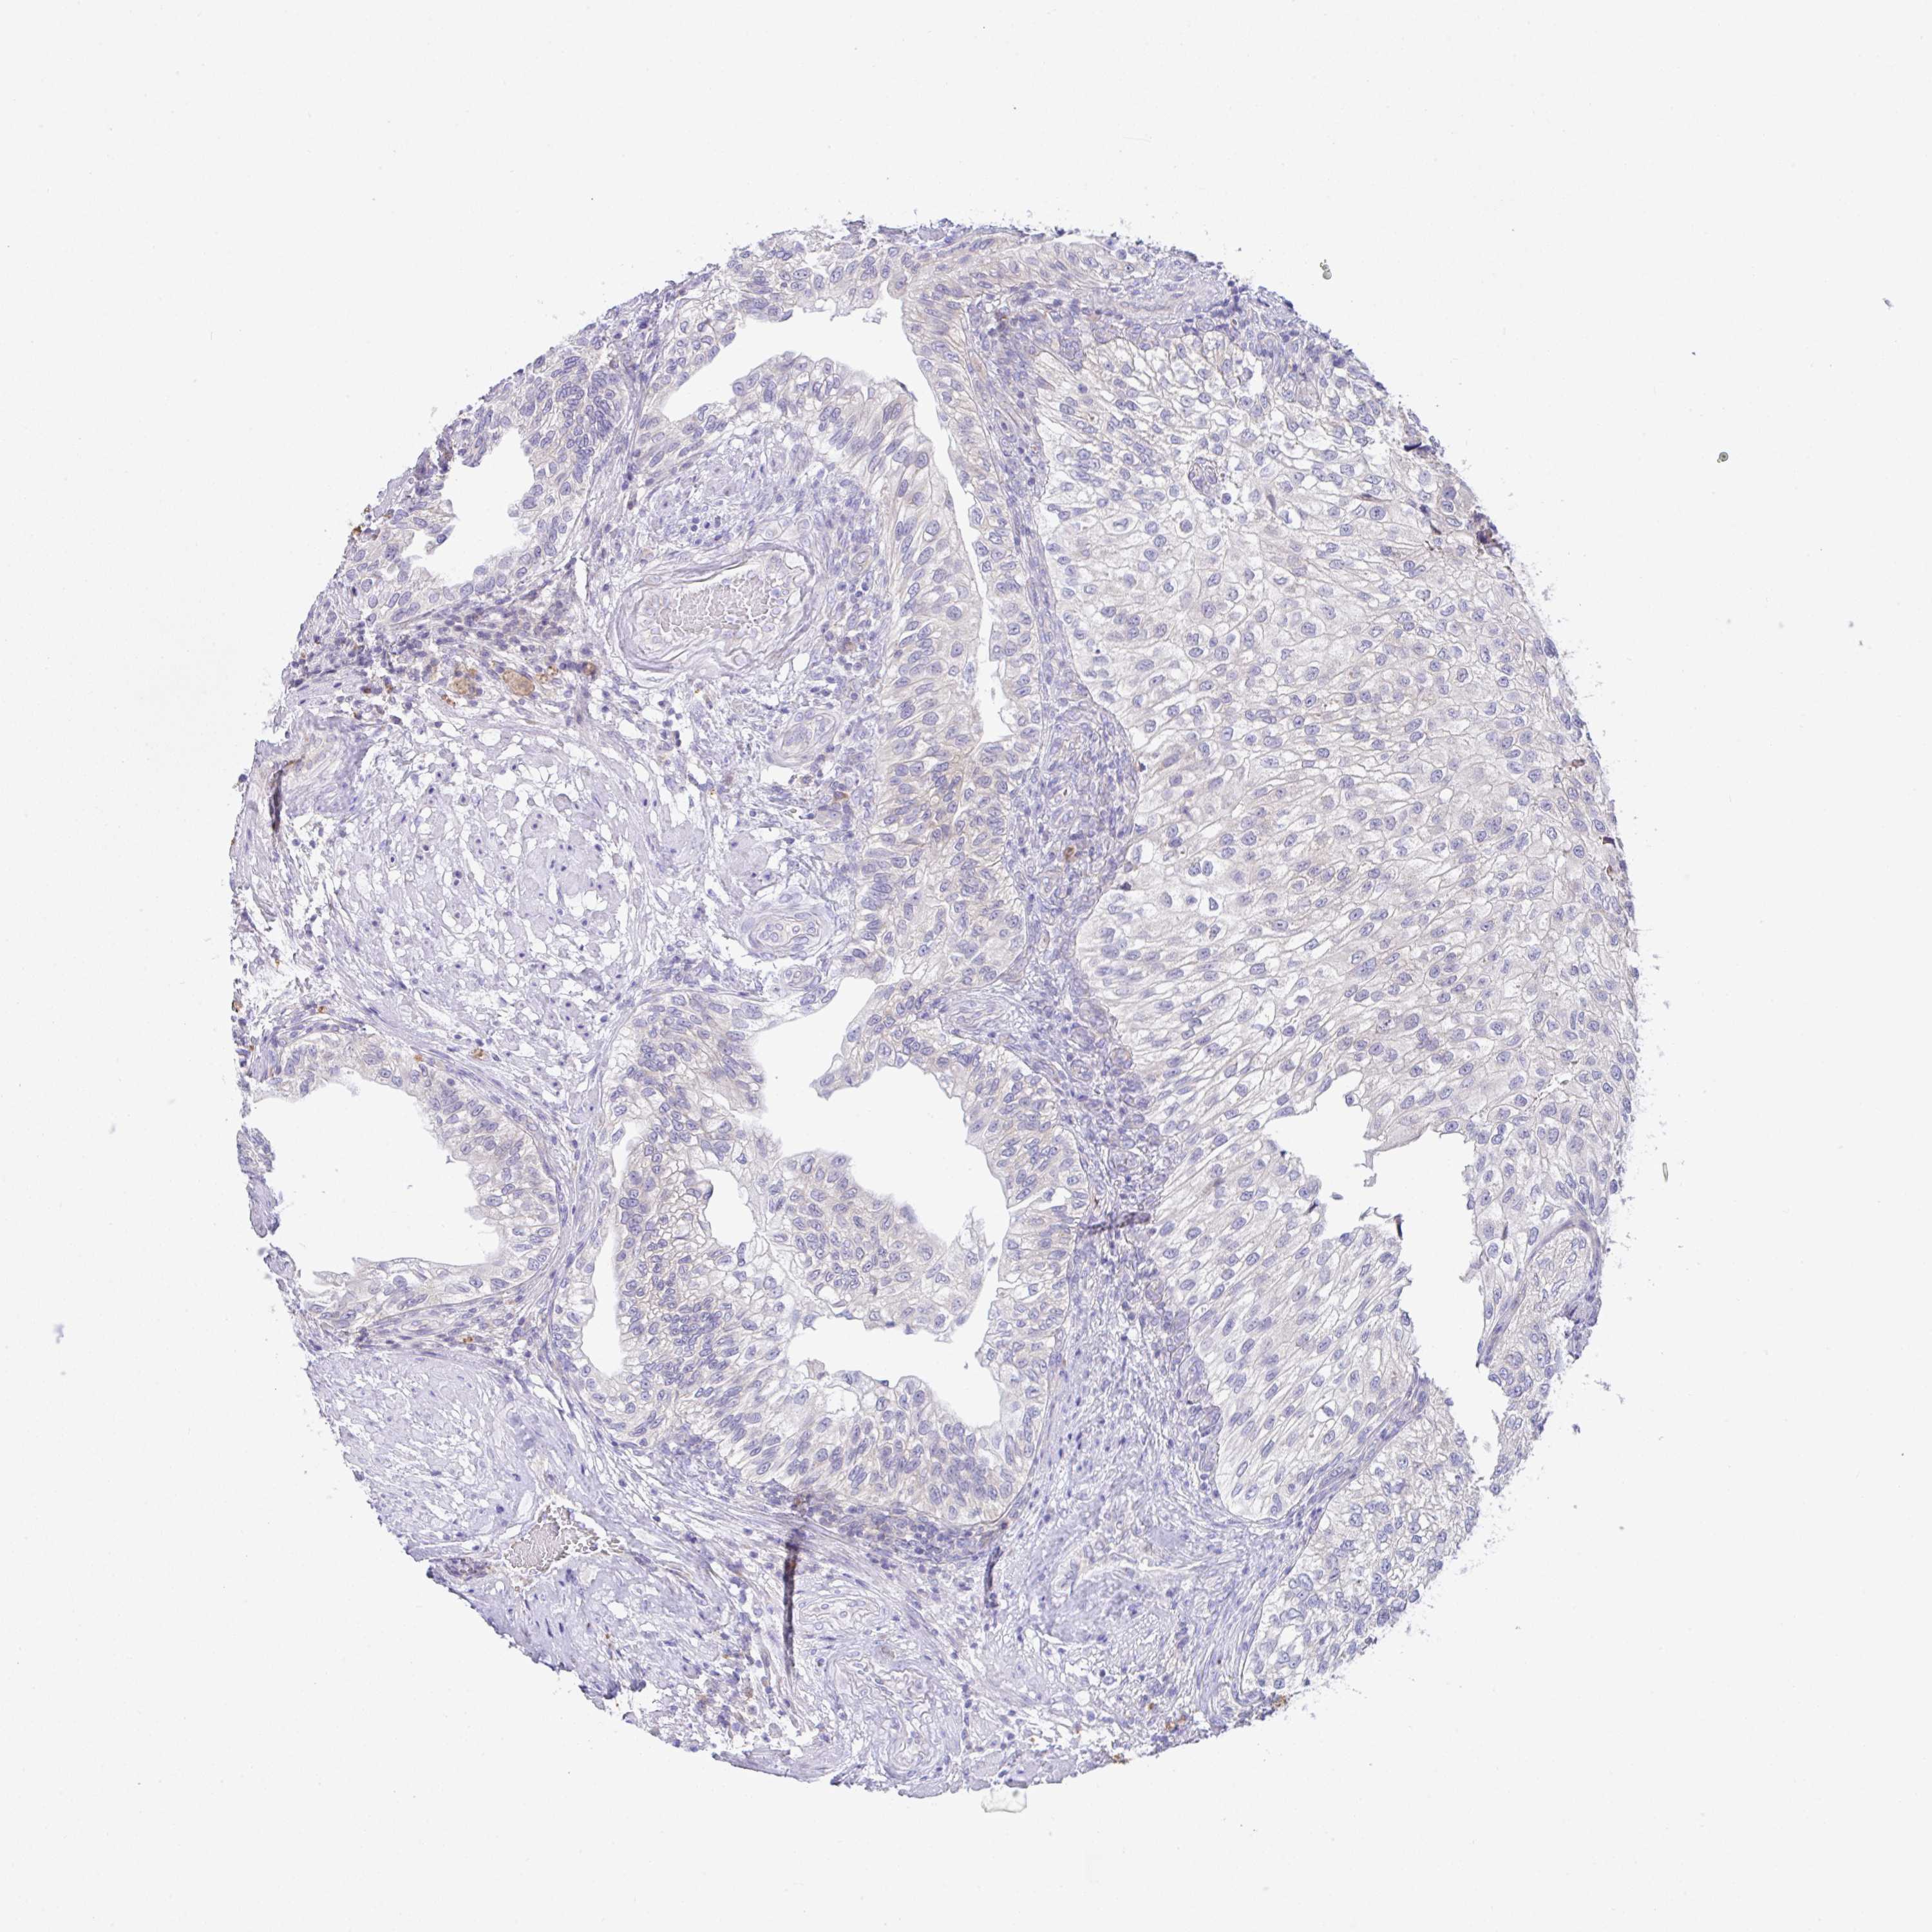

UROTHELIAL CANCER - Protein expressioni

A mouse-over function shows sample information and annotation data. Click on an image to view it in a full screen mode. Samples can be filtered based on level of antibody staining by selecting one or several of the following categories: high, medium, low and not detected. The assay and annotation is described here.

Note that samples used for immunohistochemistry by the Human Protein Atlas do not correspond to samples in the TCGA dataset.

Antibody stainingi

Antibody staining in the annotated cell types in the current human tissue is reported as not detected, low, medium, or high, based on conventional immunohistochemistry profiling in selected tissues. This score is based on the combination of the staining intensity and fraction of stained cells.

Each image is clickable and will lead to virtual microscopy that enables deeper exploration of all samples and also displays staining intensity scores, fraction scores and subcellular localization as well as patient and tissue information for each sample.

Antibody HPA059015

Staining

High

Medium

Low

Not detected

Intensity

Strong

Moderate

Weak

Negative

Quantity

>75%

75%-25%

<25%

None

Location

Nuclear

Cytoplasmic/membranous

Cytoplasmic/membranous,nuclear

Urothelial carcinoma, High grade

Urothelial carcinoma, NOS

Urothelial carcinoma, Low grade